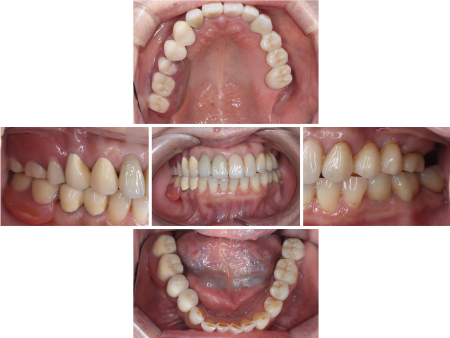

左下の奥歯3本(第2小臼歯、第1大臼歯、第2大臼歯)は、被せ物を取り除いてから再度根管治療を行い、ジルコニアクラウンを作製し装着しています。

左上の前歯(犬歯)と左上の奥歯(第1大臼歯)は被せ物を外し根管治療を行ったあと、欠損している奥歯2本(第1小臼歯、第2小臼歯)を補うジルコニアブリッジの土台として形を整え、4本つなげて装着しました。

右上の第1小臼歯と右上の犬歯は劣化した被せ物を取り除き、第1小臼歯の根管治療をしてから、それぞれ右上用のコーヌス義歯の土台歯として形を整えています。

同様に、右下の第1小臼歯と第2小臼歯も右下用のコーヌス義歯の土台歯として形を調整し、右上下それぞれの土台歯に金属の被せ物を入れて、その上から入れ歯を装着しました。

コーヌス義歯を装着後、再度歯科専門医がお口全体を確認したところ、右上の前歯2本(中切歯、側切歯)も再根管治療が必要であることがわかり、患者様に事情を説明し同意をいただいた上で、被せ物の除去と再根管治療を行ったあとジルコニアクランで修復し、治療を終了しました。